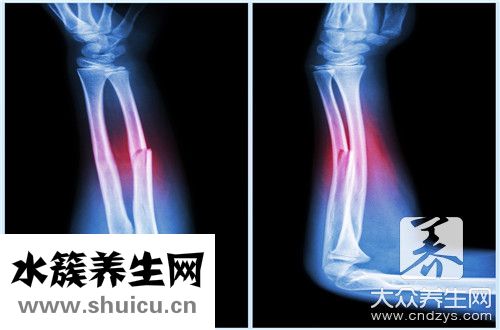

骨折一般沒有年齡區分。 所有年齡段的人有時都是骨折。 上臂骨折是生活中普遍的情況。 一般情況下,一旦發生骨折,無論什么樣的骨折,日常生活都會發生非常大的故障。 一旦發生骨折,必須馬上就診...